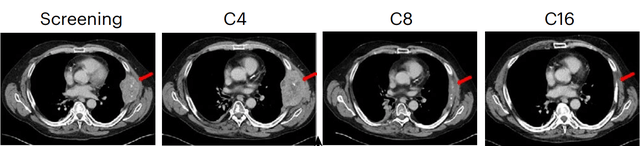

其中一名四次标准治疗均失败的肾癌患者,在该研究中肿瘤得到大幅缩小,从108mm缩小至10mm。